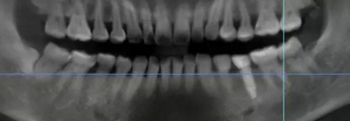

病例概述:48歲女性患者,口內(nèi)健康狀況良好,#35缺失多年,牙槽嵴頂骨寬度較窄。

#35缺失多年,導(dǎo)致#34向#35傾斜。

臨牙間距不足,因此,對(duì)種植體的位置要求極高。

術(shù)前,導(dǎo)板設(shè)計(jì)工程師,根據(jù)CBCT以及模型數(shù)據(jù),將患者的解剖結(jié)構(gòu)、軟組織形態(tài)和修復(fù)效果數(shù)字化三維重建,在設(shè)計(jì)軟件內(nèi)進(jìn)行虛擬修復(fù)體冠設(shè)計(jì),同時(shí)與臨床醫(yī)生一起,根據(jù)#35牙槽骨高度以及寬度,結(jié)合下牙槽神經(jīng)管,設(shè)計(jì)好合適的種植位點(diǎn)。

術(shù)前術(shù)后CBCT數(shù)據(jù)對(duì)比分析,植體就位準(zhǔn)確。